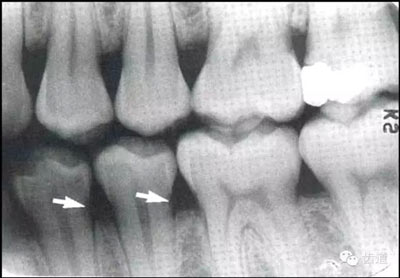

常見(jiàn)于下頜前牙區(qū),在牙根之間的牙槽骨內(nèi)并與牙長(zhǎng)軸平行的密度低的條狀影像。此為小血管進(jìn)入牙槽突的影像。